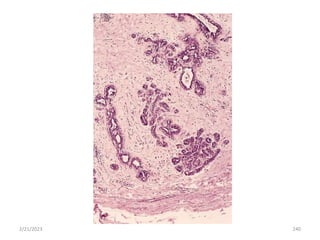

2/21/2023 206

2/21/2023 207